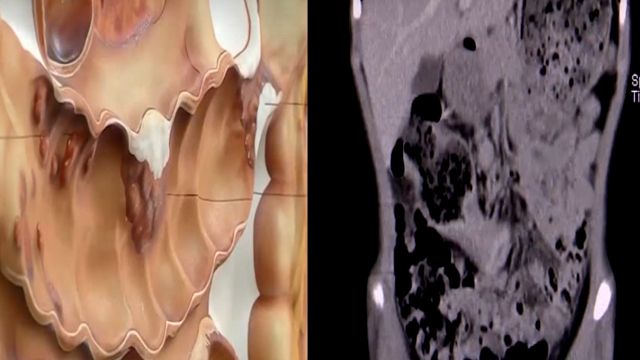

而這樣的案例在高雄也發生,而且年齡還更小,是10歲的男童,斷層掃描發現男童的腸子有5到6公分宛如乒乓球大的腫瘤,已經塞住腸道,證實罹患大腸癌第三期,是國內年齡最小的腸癌患者,雖然經過手術切掉25公分腸道跟腫瘤,不過男童仍因癌細胞擴散,還在進行化療。